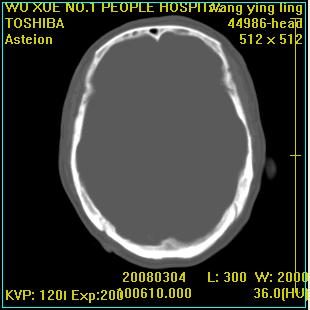

标题: CT12023:女,50岁,头部包块二月,伴轻微头痛,不伴发热。 [打印本页]

标题: CT12023:女,50岁,头部包块二月,伴轻微头痛,不伴发热。

这种病例还是比较多见,起源于颅骨板障,向颅内和颅外生长,考虑血管瘤或嗜酸性肉芽肿,要是有增强ct就好了。

多发溶骨性破坏,骨嗜酸性肉芽肿可能,转移瘤待排除,建议进一步检查。

破坏区边界较清楚,还是考虑良性病变---嗜酸性肉芽肿可能。

颅骨多处破坏伴软组织肿块,考虑为转移瘤可能性大。

病灶呈溶骨性骨破坏,考虑嗜酸性肉芽肿可能转移瘤不除外建议追查病史并进一步检查